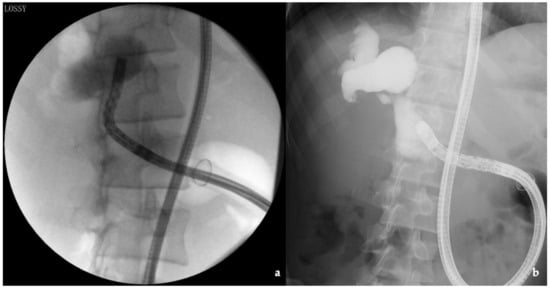

3.4. Intussusception Antireflux Valve